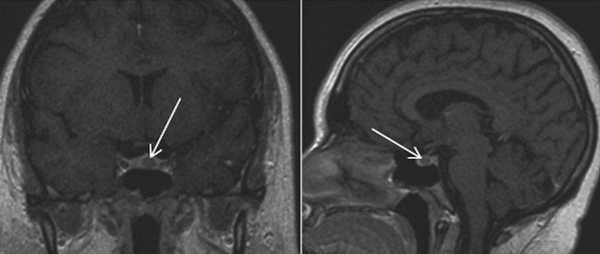

Микроаденома гипофиза (указана стрелкой) на снимке МРТ

Микроаденома гипофиза на снимках МРТ имеет ряд характерных признаков:

- неоднородная структура;

- округлая форма;

- очаг имеет гипоинтенсивный сигнал на Т1-взвешенных изображениях;

- выраженная граница, отделяющая образование от здоровых тканей;

- при наличии кровоизлияний и кист наблюдается усиление сигнала на Т2-взвешенных изображениях.

Для лучшей визуализации микроаденомы применяют динамическое контрастирование. Метод подразумевает использование короткого временного промежутка, когда велика разница сигналов между новообразованием и участками с нормальной структурой. На снимках МРТ с динамическим усилением аденома гипофиза в первой фазе исследования выглядит как гипоинтенсивный очаг на фоне умеренно контрастирующих здоровых тканей железы.

МРТ гипофиза с контрастом. После введения контрастного вещества в гипофизе происходит его накопления и он выглядит светлым. Только участок опухоли не накапливает контрастное вещество и выглятит темным (стрелка).